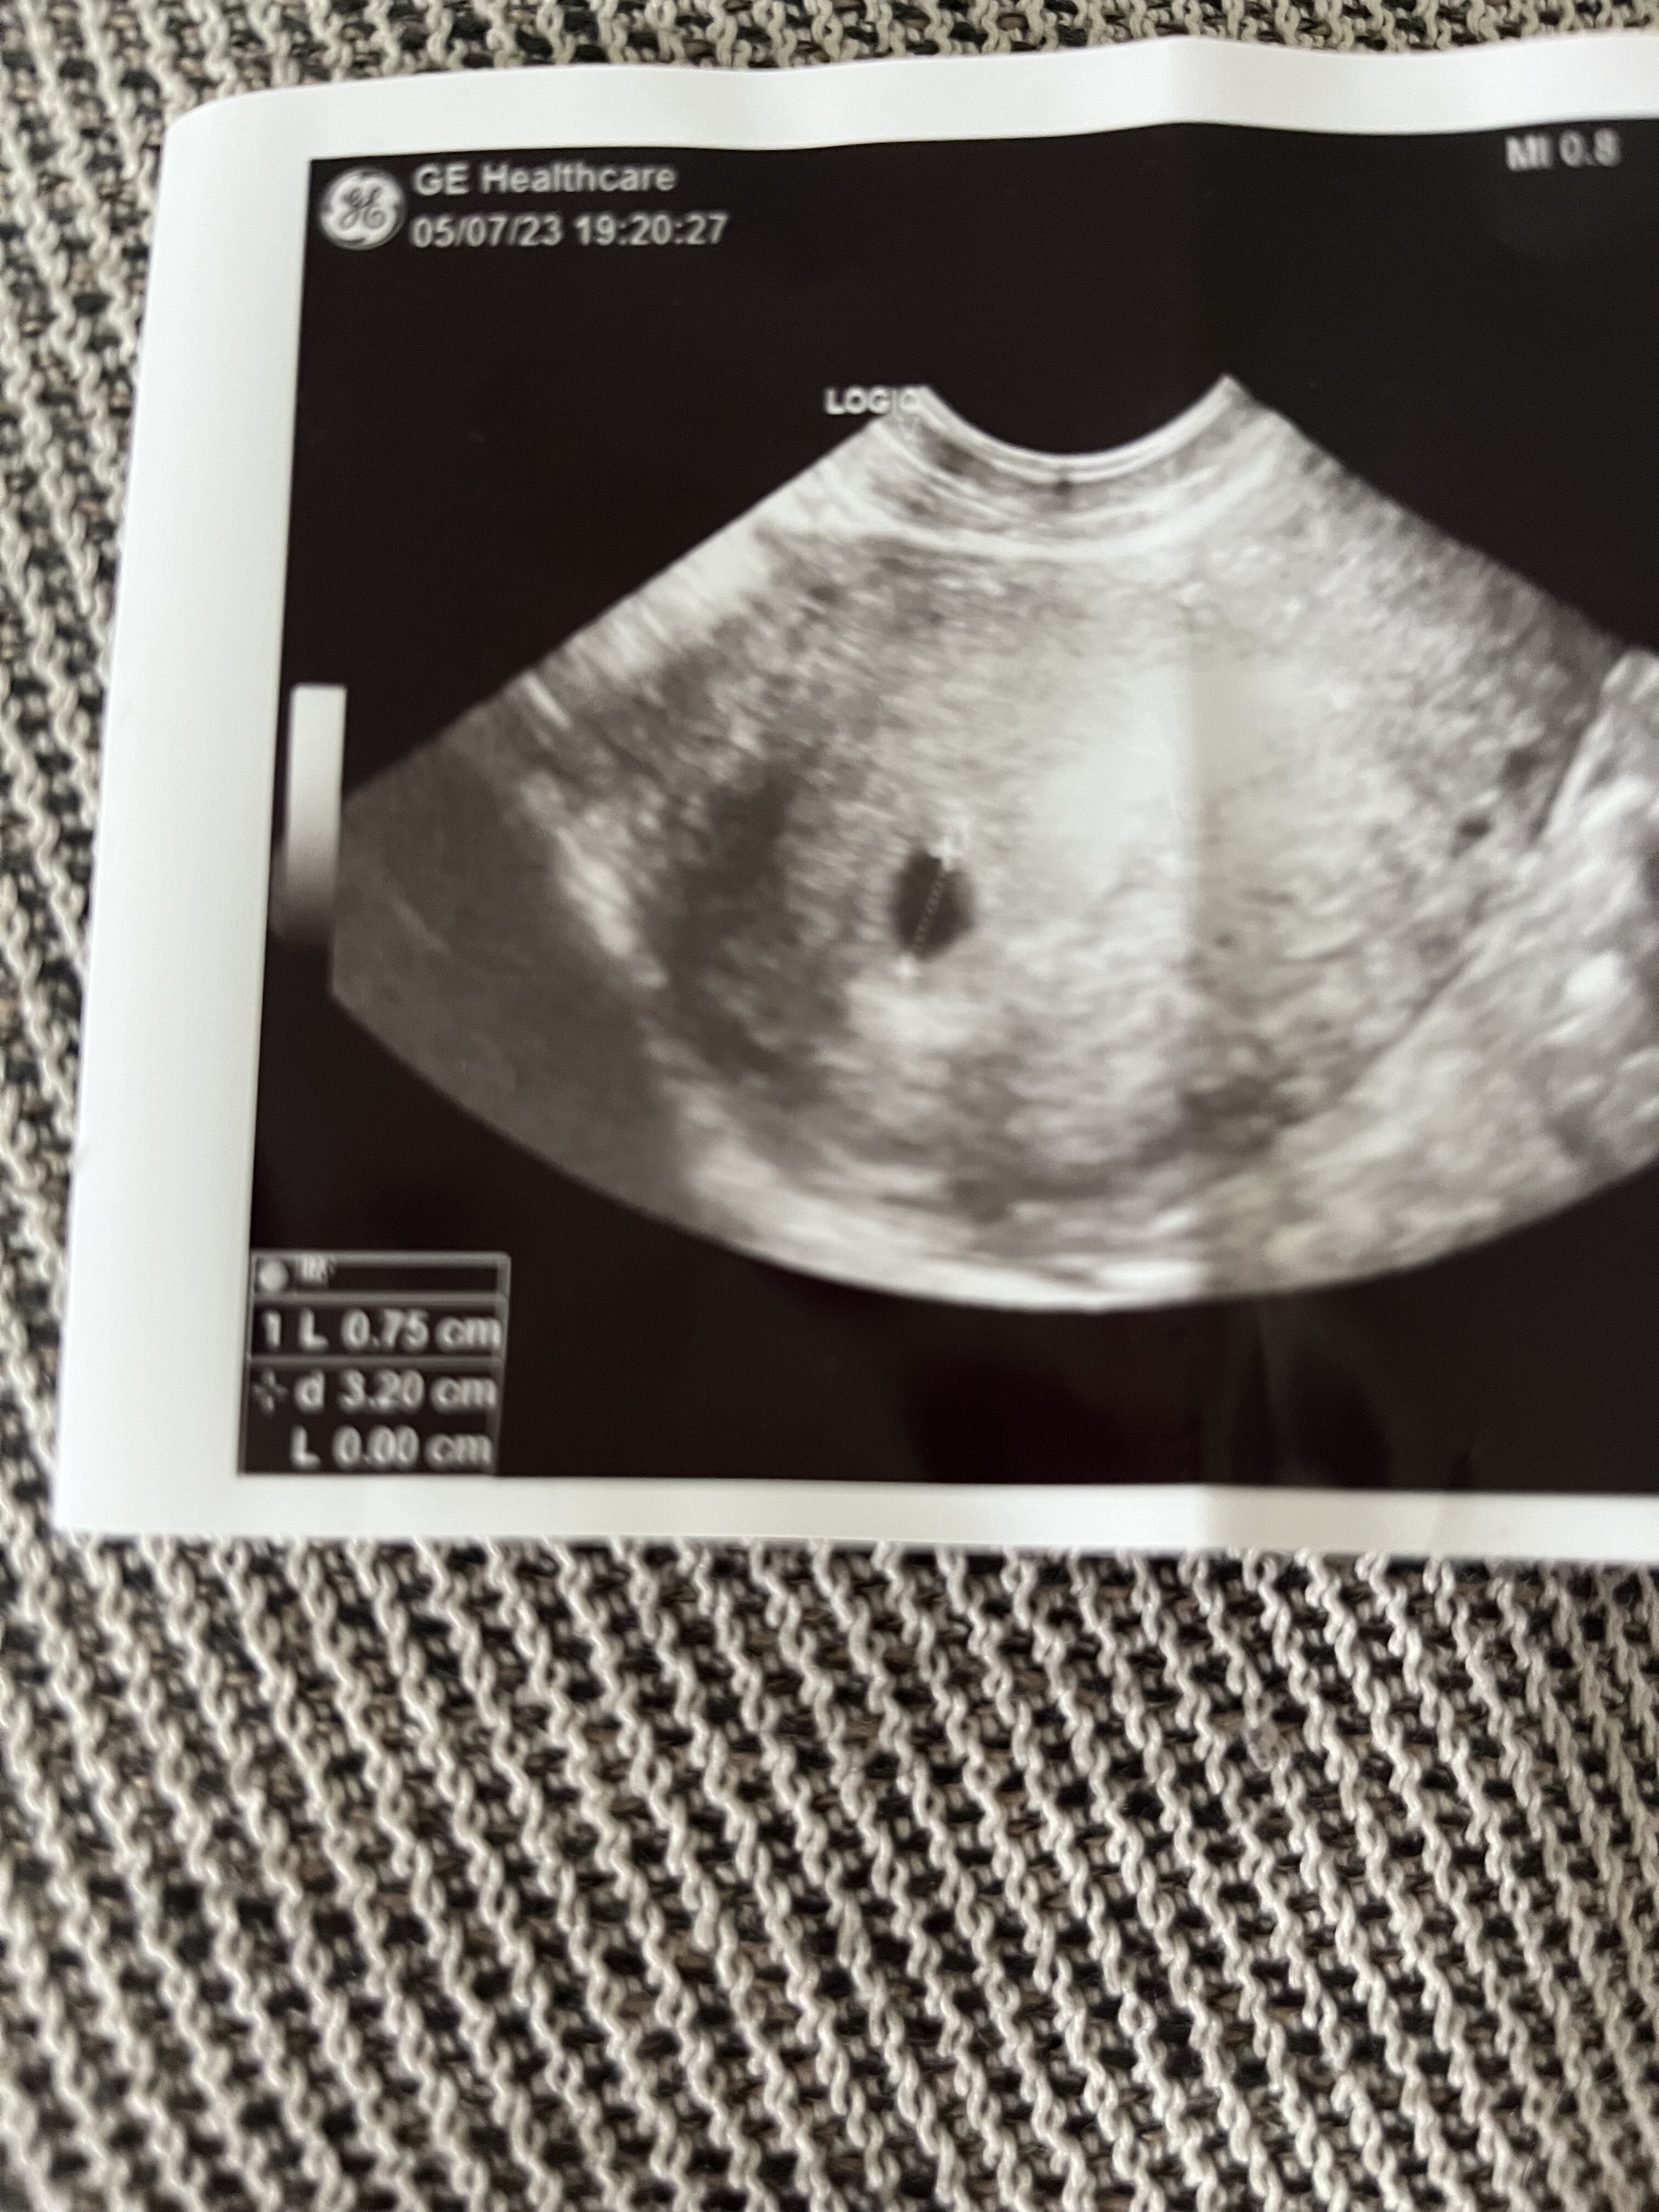

Z tymi wymiarami tez mam problem bo mimo, ze to moja 3 ciąża i powinnam być oblatana to jedynie się domyślam, że to wymiar 0,75? Czym jest ten drugi wymiar 3,2?

ja z tego usg tez nie wiem ktory to wymiar pecherzyka, ale moze ktos inny bedzie wiedzial ktora to liczba i napisze 🙂 Poczekaj na wyniki bety, zobaczysz jaka tam bedziesz miala wartosc, podobno przy becie powyzej 10 tys juz powinno byc widac zarodek z bijacym sercem